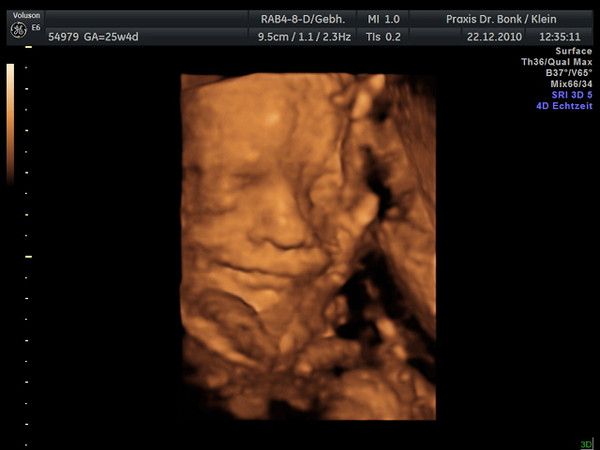

Krümel hat in SSW20+0T(21.SSW) eine Größe von 21cm erreicht und wiegt schon 280g